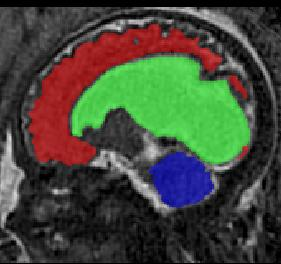

Limiting failures of machine learning systems is of paramount importance for safety-critical applications. In order to improve the robustness of machine learning systems, Distributionally Robust Optimization (DRO) has been proposed as a generalization of Empirical Risk Minimization (ERM). However, its use in deep learning has been severely restricted due to the relative inefficiency of the optimizers available for DRO in comparison to the wide-spread variants of Stochastic Gradient Descent (SGD) optimizers for ERM. We propose SGD with hardness weighted sampling, a principled and efficient optimization method for DRO in machine learning that is particularly suited in the context of deep learning. Similar to a hard example mining strategy in practice, the proposed algorithm is straightforward to implement and computationally as efficient as SGD-based optimizers used for deep learning, requiring minimal overhead computation. In contrast to typical ad hoc hard mining approaches, we prove the convergence of our DRO algorithm for over-parameterized deep learning networks with ReLU activation and a finite number of layers and parameters. Our experiments on fetal brain 3D MRI segmentation and brain tumor segmentation in MRI demonstrate the feasibility and the usefulness of our approach. Using our hardness weighted sampling for training a state-of-the-art deep learning pipeline leads to improved robustness to anatomical variabilities in automatic fetal brain 3D MRI segmentation using deep learning and to improved robustness to the image protocol variations in brain tumor segmentation. Our code is available at https://github.com/LucasFidon/HardnessWeightedSampler.